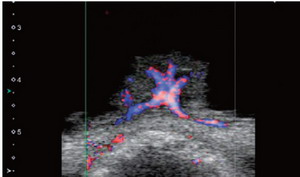

ÀÌ Áß Áö³­ 2014³â °³¹ß¿¡ ¼º°øÇÑ SMI¢â±â¼úÀº ±âÁ¸ÀÇ ÃÊÀ½ÆÄ ¿µ»ó¿¡¼­ ±¸ÇöÇϱ⠾î·Á¿ü´ø º´º¯ ³» Àú¼Ó Ç÷·ù¸¦ °íÇØ»óµµ ¿µ»óÀ¸·Î ±¸ÇöÇÏ´Â µµ½Ã¹ÙÀÇ Çõ½ÅÀûÀÎ µµÇ÷¯ ±â¼úÀÌ´Ù.

ÁÖâ¾ð ´ëÇ¥´Â ¡°±×·¯³ª SMI¢â ±â¼ú·Î ´ÙÂ÷¿ø ÇÊÅ͸µ(Multi-dimensional Filtering)ÀÌ °¡´ÉÇØÁ® Àú¼Ó Ç÷·ùÁ¤º¸¸¦ º¸Á¸ÇÏ°í ±×°ÍÀ» °íÇØ»óµµ·Î ±¸ÇöÇÒ ¼ö ÀÖ°Ô µÆ´Ù¡±°í °­Á¶Çß´Ù.

¶ÇÇÑ SMI¢â ±â¼úÀº Ç÷·ùÀÇ ¼Óµµ°¡ ´À¸° ¸²ÇÁÀýÀ» º¸±â¿¡ ¿ëÀÌÇÏ´Ù. Neoplasm(Á¾¾ç), Inflammation(¿°Áõ)À» Àß º¼ ¼ö ÀÖ´Â ÀåÁ¡µµ °®°í ÀÖ´Ù.

ÁÖâ¾ð ´ëÇ¥´Â ¡°º¸Åë Á¾¾çÀ̳ª ¿°ÁõÀÌ »ý±â¸é ÁÖº¯ Ç÷°üÀÇ Ç÷·ù·®ÀÌ ºü¸£°Ô Áõ°¡ÇÏ°Ô µÈ´Ù¡±°í ¼³¸íÇß´Ù.

±×´Â ¡°ÀÌ ¶§ SMI¢â[»çÁø éÓ]¸¦ »ç¿ëÇϸé ÀÌ·¯ÇÑ Ç÷·ùÀÇ È帧À» Àß È®ÀÎÇÒ ¼ö ÀÖ´Ù¡±°í ¸»Çß´Ù.

ÀÌ¾î ¡°ÀÓ»óÀûÀ¸·Î´Â Àå, ¾µ°³ º®ÀÇ ¿°ÁõÀ» È®ÀÎÇÒ ¼ö ÀÖ°í, ƯÈ÷ °£¼¼Æ÷¾Ï(Hepatocellular Carcinoma)°ú ÀÌ½ÄµÈ ½ÅÀåÀÇ Ç÷·ù ÆÐÅϱîÁöµµ È®ÀÎÀÌ °¡´ÉÇÏ´Ù¡±°í µ¡ºÙ¿´´Ù.